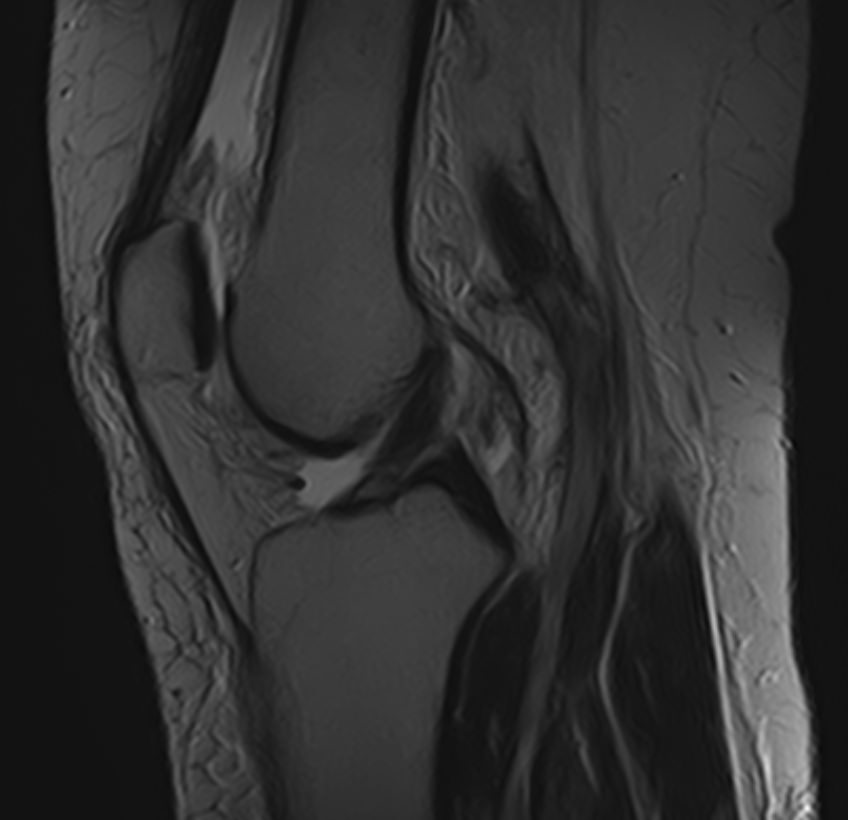

Пояснично-крестцовый отдел позвоночника выполняет основную опорную функцию, поддерживая устойчивость тела. Нижние отделы позвоночника и крупные суставы нижних конечностей, в частности, коленные суставы, испытывают интенсивные нагрузки, поэтому часто подвержены развитию воспалительных и дегенеративно-дистрофических заболеваний.

При сочетанном поражении этих анатомических областей целесообразно проведение комплексной МРТ, включающей обследование пояснично-крестцового отдела позвоночника и коленных суставов.

Томограф позволяет детально визуализировать состояние всех анатомических структур позвоночного столба на исследуемом уровне, костные структуры колена и окружающие мягкие ткани данных анатомических областей, включая мышцы, связки, нервные сплетение, сосуды.